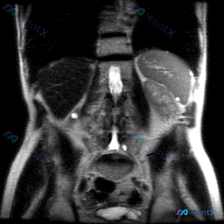

今天看到一份腹部冠状位MRI T2WI的资料,本来是看“脾脏病变”的,但肾脏的表现实在太抢眼了,不过仔细理一理,这里面其实藏着一个很容易掉的陷阱。 先整理一下影像里的关键信息: 影像核心表现 1. 双侧肾脏:体积增大,弥漫分布多发大小不等的囊性病灶,T2WI上是亮白的极高信号(和脑脊液差不多),囊壁...

看到一份影像资料,临床问的是“脾脏病变”,但拿到的T2加权冠状位报告重点却在右肾,感觉这个逻辑断层很有讨论意义,整理一下思路和大家分享。 先看影像里的客观所见 - 肝脏、胆囊、胆道:肝实质信号均匀,胆囊是生理性高信号,胆道没看到明显扩张; - 脾脏:报告写“形态尚可,实质信号未见明显异常”; - 右...